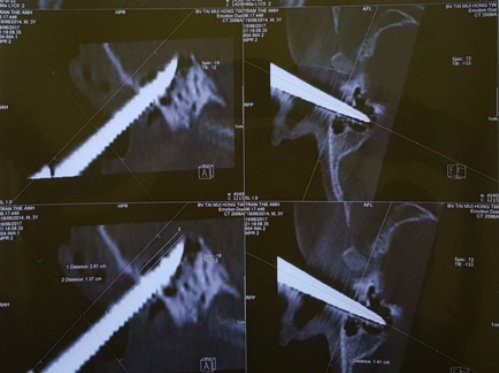

Kiểm tra nhanh, các bác sĩ nhận thấy cháu bé may mắn không bị tổn thương thần kinh số 7. Phim chụp X-quang phát hiện mũi kéo đâm sâu vào trong tai khoảng hơn 3 cm. Sau khi gây mê nội khí quản, các bác sĩ đã quyết định rút trực tiếp dị vật.

Phim chụp X-quang cho thấy mũi kéo đâm sâu vào bên tai bệnh nhi. (Ảnh: M.T)

“Mũi kéo đâm xuyên ống tai ngoài, đâm vào vùng xương chũm khoảng 1,3 cm nhưng may mắn mũi kéo to lại đâm chéo nên toàn bộ phần tai giữa, tai trong, màng nhĩ bệnh nhi vẫn còn nguyên, không ảnh hưởng đến thính lực”, bác sĩ Thắng cho biết.